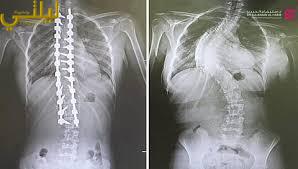

مستشفى الدكتور سليمان الحبيب بالقصيم يجرى عملية ناجحة لتقويم “جنف” بزاوية “95” درجة

أجرى مستشفى الدكتور سليمان الحبيب بالقصيم، عملية جراحية معقدة، لتقويم انحراف متزايد في العمود الفقري “جنف”، وتثبيت ودمج الفقرات لفتاة،…